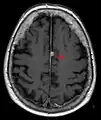

MRI image of the surface of the brain.

T1 (note CSF is dark) with contrast (arrow pointing to meningioma of the falx)